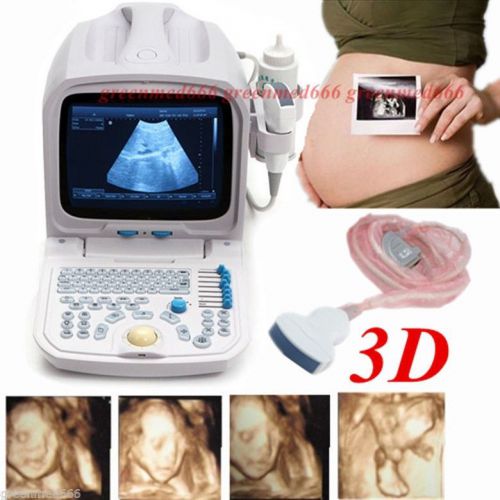

| Model | RUS-9000F |

3D PC Platform Full Digital Portable Ultrasound Scanner Machine +Convex Probe CE